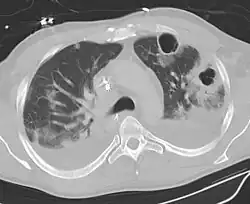

Computed tomography (CT) scan of chest showing bilateral pneumonia with abscesses, effusions, and caverns. 37-year-old male.

Lung abscesses are often on one side and single involving posterior segments of the upper lobes and the apical segments of the lower lobes as these areas are gravity dependent when lying down. Presence of air-fluid levels implies rupture into the bronchial tree or rarely growth of gas forming organism.